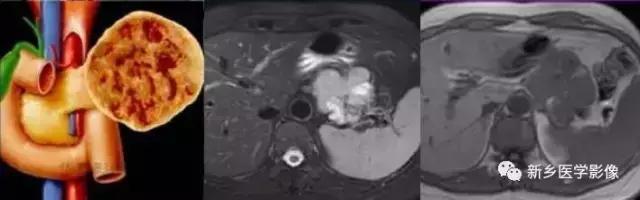

1.病理:本病的起源尚有争议,有认为起源于胰腺外分泌腺细胞、内分泌腺细胞或具有向内外分泌腺分化的全能细胞等学说, 肿瘤可发生于胰腺任何部位, 一般较大, 常见的直径为5 ~ 8cm 。肿瘤周围有较厚的纤维包膜, 边界清楚,常突出于胰腺外。瘤体剖面可见明显出血和坏死, 大的坏死区可形成囊腔, 内

含血性或胶冻样物,构成囊实相间的结构,30 %左右的肿瘤周边可见钙化。病变内富有薄弱血管为本病的又一病理学特点。镜下可见胞质呈嗜酸性的小肿瘤细胞围绕纤维血管形成假乳头状结构。免疫组化及电镜示肿瘤同时具有内分泌和外分泌组织成分。

2.影像学诊断:CT 、M RI 上, 本病表现为胰腺边界清楚的大肿块, 囊实相间, 实性部分主要位于病变周边,有强化;囊性部分主要位于病灶中心区域, 囊变区密度较高, CT 值40 ~50Hu 。30 %的患者病变周边可见钙化。由于病变内常有出血,T1W I 上可见不均匀高信号, T 2WI 上见不均匀低信号 。M RCP 或E RCP 示胰管受压、移位或中断。